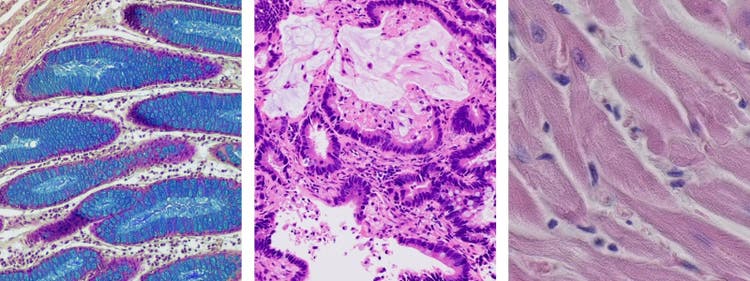

La microscopie en fond clair peut être utilisée pour étudier un large éventail d’échantillons (cellules, tissus, minéraux, fibres, etc.). Il s’agit donc d’un outil polyvalent, qui peut être utilisé dans de nombreux domaines de recherche ainsi que dans différentes industries.